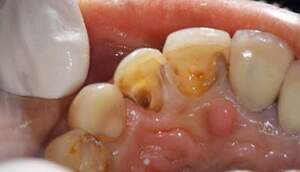

左上2番目の前歯が変色。 原因は失活歯であったことと、CRの周囲でカリエスになっていたため。 また、そのカリエスも大きく、このままでは保存が不可能であった。 そのため歯を挺出させて保存することとした。 |

カリエスが大きく、舌側では歯肉より上に残存歯質がなくなってしまっている。このままではコア、クラウンの接着ができないため、歯を歯肉より上にだすことが重要です。

右の写真では歯肉の上に歯が一周のこり、その上にコアが入っているのがわかります。

左上2は広範囲にわたってCRが充填されているのがわかります。またその周囲に透過像があり、カリエスになっていることもわかります。